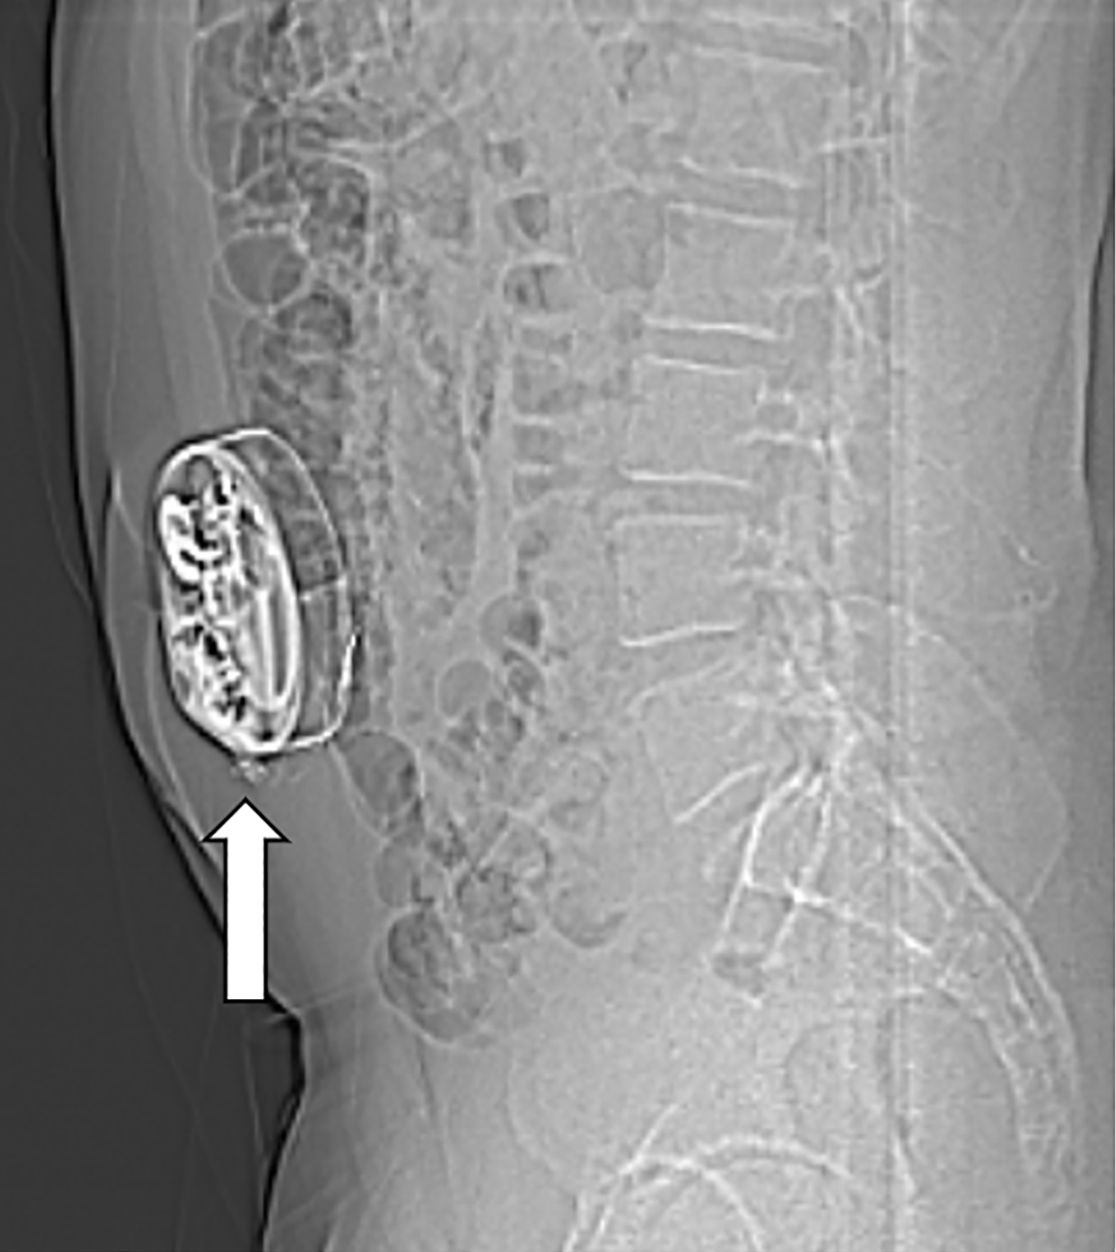

Am Bauch implantierte Medikamentenpumpe (Pfeil)

Bei Patienten mit schwerer Spastik oder chronischen Schmerzen, die nicht ausreichend auf herkömmliche medikamentöse Therapien ansprechen, kann die Implantation einer Schmerzpumpe eine effektive Lösung darstellen. Diese Pumpe ermöglicht die direkte Abgabe von Schmerzmitteln oder muskelentspannenden Medikamenten in den Nervenwasserraum (intrathekal), was eine deutlich gezieltere Wirkung mit geringeren Nebenwirkungen ermöglicht als bei in Tablettenform eingenommenen Medikamenten.

Das Pumpensystem besteht aus einem kleinen Schlauch, welcher in den Nervenwasserraum eingebracht wird und mit der Pumpe verbunden ist. Die Pumpe wird meist am Bauch unter der Haut implantiert und ermöglicht, dass die Dosierung der Medikamente exakt an die Bedürfnisse angepasst werden kann. Es ist eine regelmäßige Wiederbefüllung der Pumpe mit den Medikamenten notwendig, was ähnlich wie bei einer Blutabnahme von außen erfolgt.